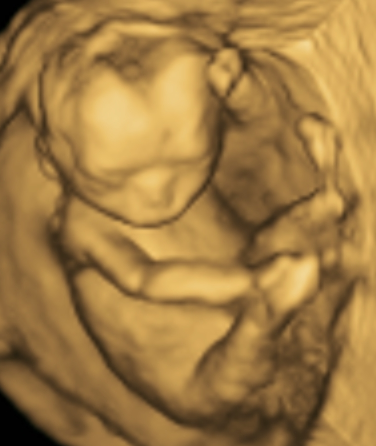

Contamos con gran variedad de estudios como abdomen, pélvico, tiroides, obstétrico 3D y 4D, protocolos maternofetales, estructural, entre otros.

MATERNO FETAL

PERFIL BIOFÍSICO FETAL